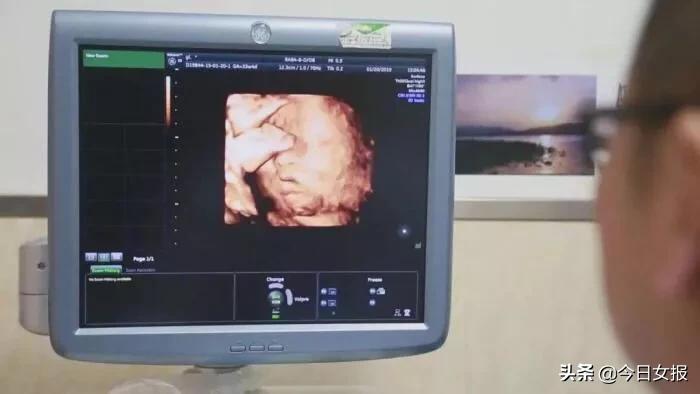

在对移植子宫连续监测后,为提高胚胎移植成功率,专家团队采取中西医结合的方法,改善杨华子宫内膜情况,为胚胎着床做好准备。2018年6月13日,妇产科王西林教授实时监测超声,在超声“慧眼”精确指引下,妇产科黄艳红教授小心翼翼地将冷冻胚胎植入移植的子宫内。14天后,复苏胚胎着床,杨华成功妊娠,这已是第五次尝试。妊娠早期,杨华出现妊娠剧吐、先兆流产的症状,妊娠中晚期出现胎儿生长受限,先后4次住院进行保胎等治疗。

整个孕期,为避免出现并发症、确保母婴健康,妇产科、泌尿外科专家团队结合杨华身体情况,制定了个体化免疫抗排斥用药等方案,并定期进行超声、血药浓度、激素水平等监测。根据监测结果,实时调整用药,保证胎儿羊水、体重、胎心等生长发育指标处于正常范围。